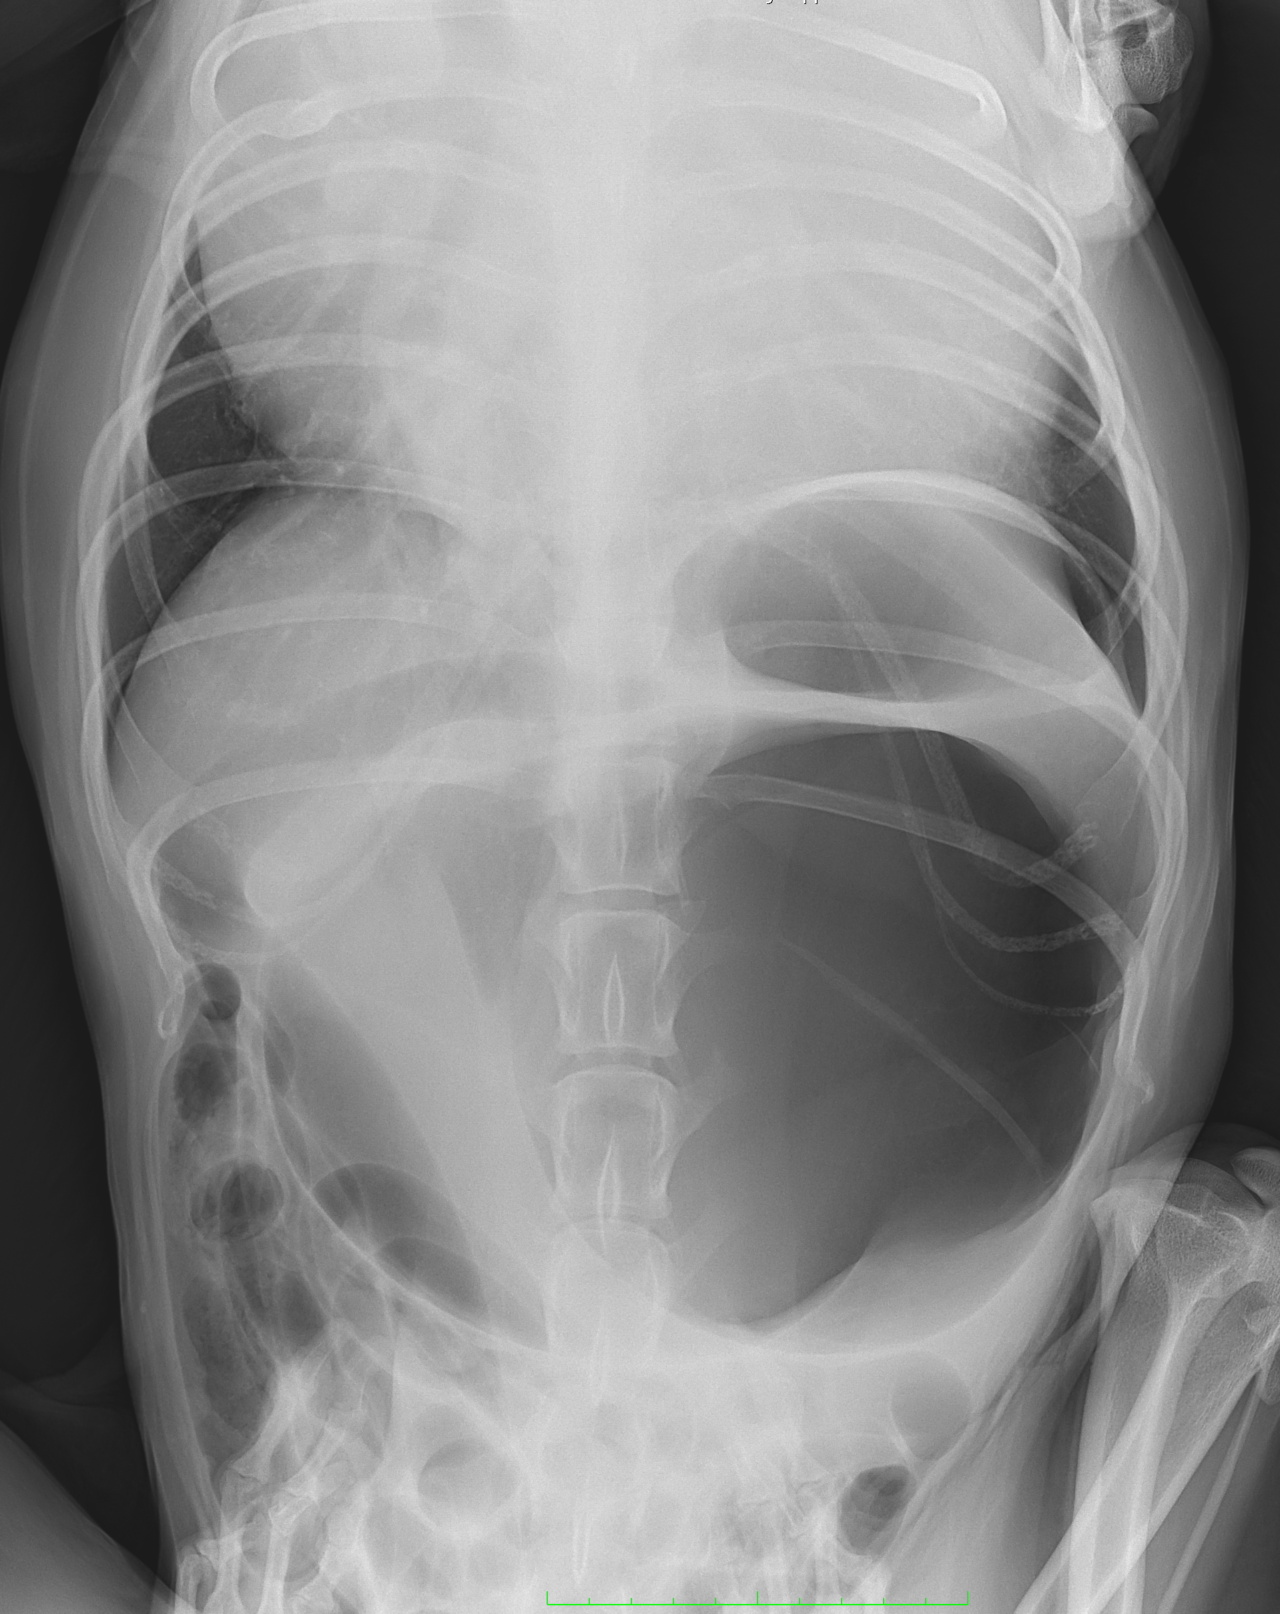

高齢(12歳)のアフガンハウンドが吐きたそうだけど、何も出てこない。次第に起立出来なくなったとのことで夜間に救急で来院しました。症状とエックス線検査から胃捻転と診断しました。また聴診時に心音は遠く、聴取出来ませんでした。胸部エックス線検査においてムーンハートが確認されました。超音波ガイドで出血性心のう水を2リットル抜去しました。バイタルサインが落ち着いたところで胃捻転整復術を実施しました。その後も出血性心のう水は貯留傾向にありました。高齢であることから血管肉腫が疑われましたが、各種画像診断においても腫瘤の存在はなくまた細胞診においても血管肉腫の可能性は低いものと判断しました。胃捻転から2週間後、心膜の生検と再発性の心膜貯留を回避する目的で心膜切除術を実施しました。心膜は顕著に肥厚し、線維化を伴っていました。病理検査の結果をもとに内科療法を併用する予定です。高齢ながら頑張ってくれました。